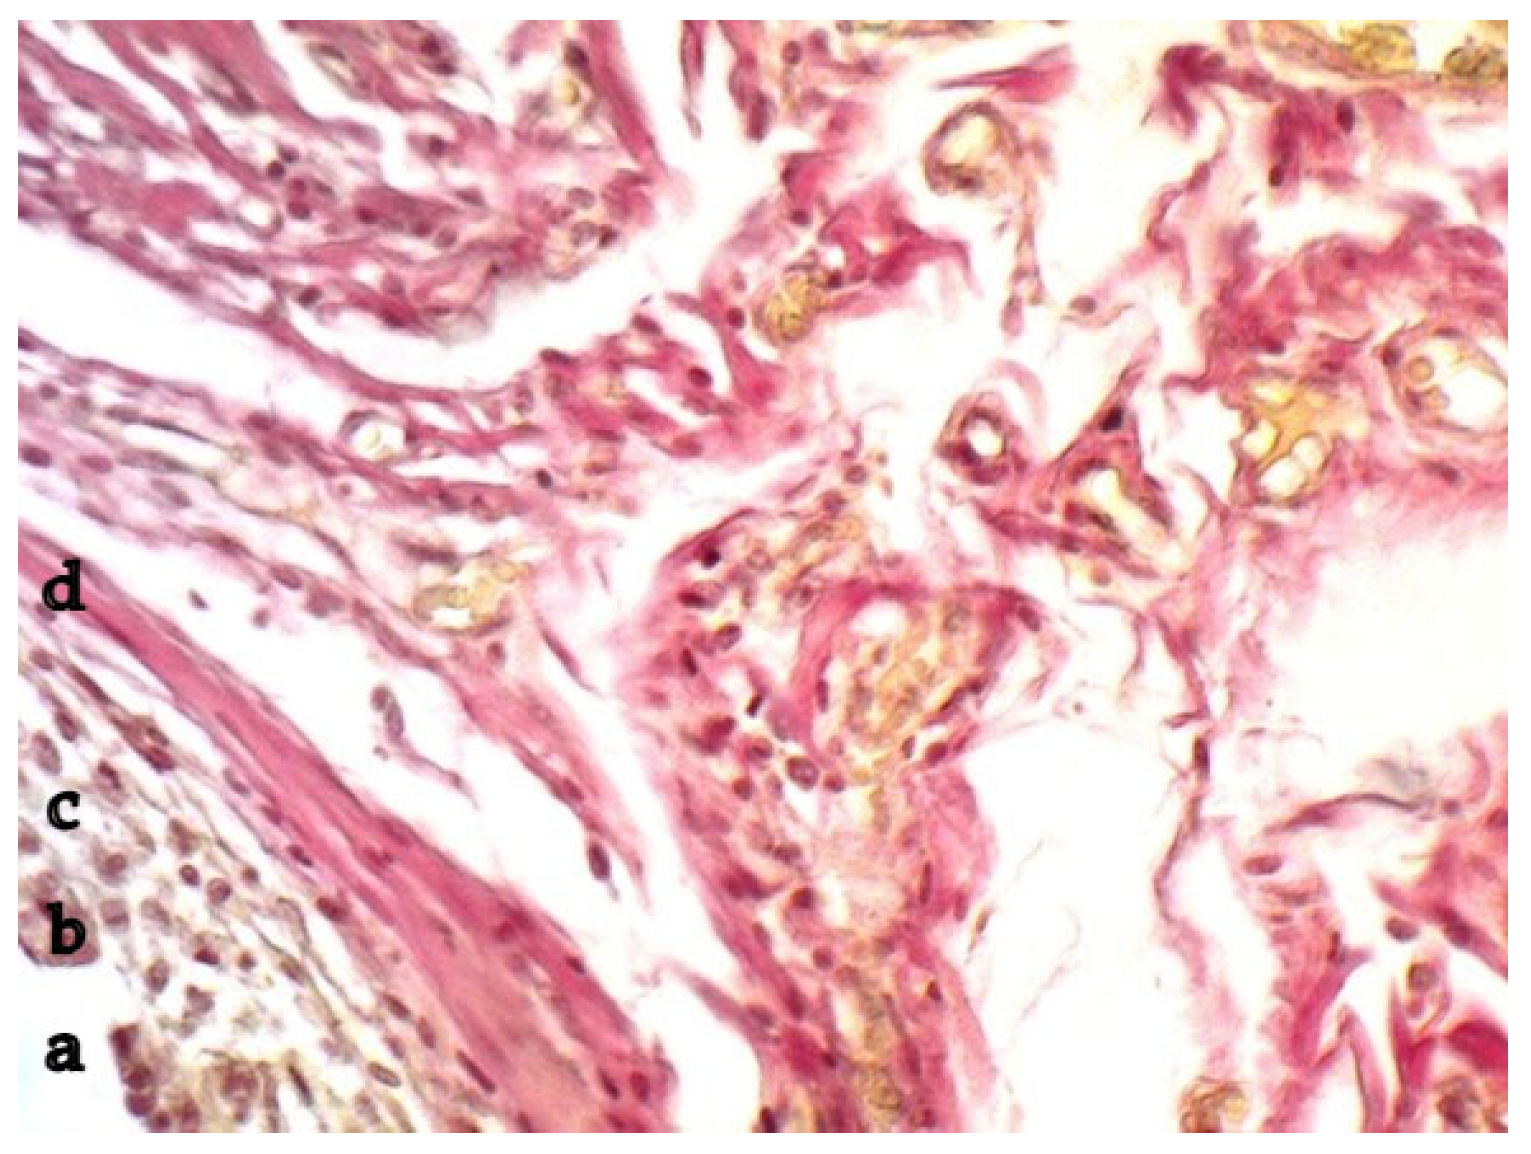

2.1. Tissue Response to Polypropylene (Macropreparation, Morphometry)